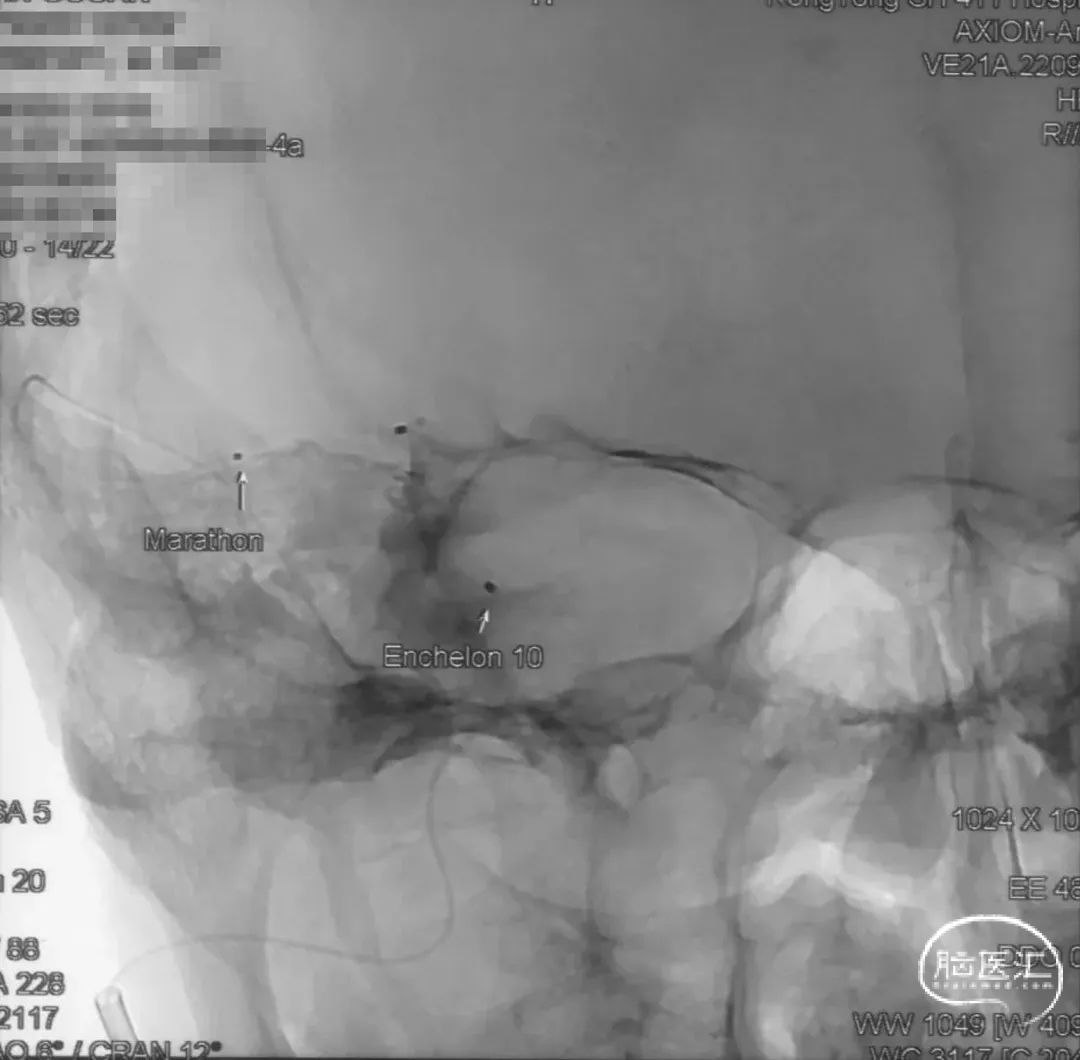

选取工作角度,正侧位造影

Echelon-10微导管在ASAHI 0.010微导丝导引下经右侧脑膜中动脉分支超选至瘘口,可见瘘口口径大,微导管直接越过瘘口,进入引流静脉起始部。

Marathon微导管在ASAHI 0.010微导丝导引下经右侧脑膜中动脉分支超选至瘘口近端。

经Marathon微导管手推造影明确微导管位于瘘口动脉端,Echelon-10微导管位于瘘口引流静脉起始端处扩张的静脉球内。

由于瘘口流量大,为了防止栓塞材料过度弥散,并逃逸至深静脉,首先通过Echelon-10微导管向静脉球内填入Feng 12/40、Feng 10/30两枚弹簧圈,限制后续液态栓塞材料仅在静脉起始部弥散。

随后回撤Echelon-10微导管,并通过Echelon-10微导管和Marathon微导管交替注入Onyx-34、Onyx-18,此时可见Onyx首先被血流冲至静脉球内,但被弹簧圈篮筐限制,并在瘘口范围内弥散。

通过“注射-停顿-再注射”,Onyx进一步在瘘口及供血动脉段和引流静脉起始部弥散满意